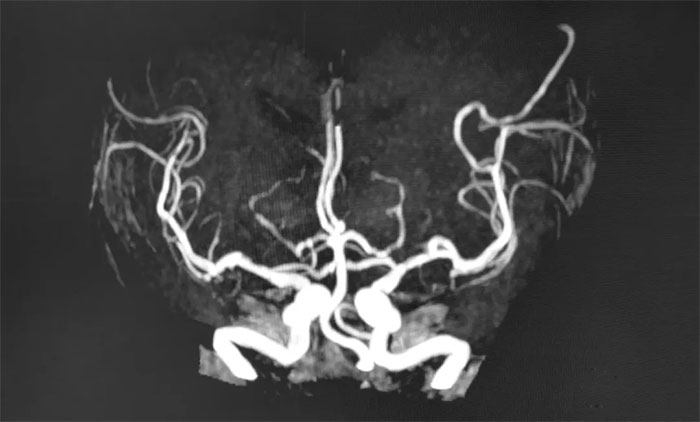

MRA是基于饱和效应、流入增强效应、流动去相位效应显示血管,可发现血管狭窄和闭塞的部位,以及血管病变(动脉瘤、动脉畸形等)。

MRA包括直接MRA与增强MRA(CE-MRA),二者各有优势。直接MRA不用对比剂,简便无创,成本低,对于显示血管非常有其实用价值,已经成为临床不可少的检查方法。CE-MRA对血管腔的显示比直接MRA更为可靠,出现血管狭窄的假象明显减少,血管狭窄程度的反映比较真实。对于脑血管病高危人群来讲,定期做脑血管磁共振(MRA)检查非常重要!

▲ MRA显示颅底动脉多发局灶性狭窄